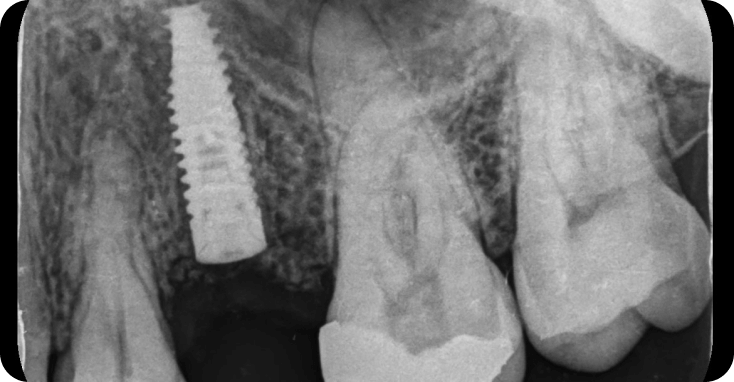

Implantes

Son tornillos en titanio que reemplazan las raices de los dientes.

Implantes de uso en la clínica

MISS, ADIN , ALPHABIO.

Perimplantitis (Infección del hueso alrededor del implante) suscausas pueden ser mala higiene, bruxismo, pacientes diabeticos no controlados, periodontitis adyacentes. Rechado del organismo 5%.

Casos